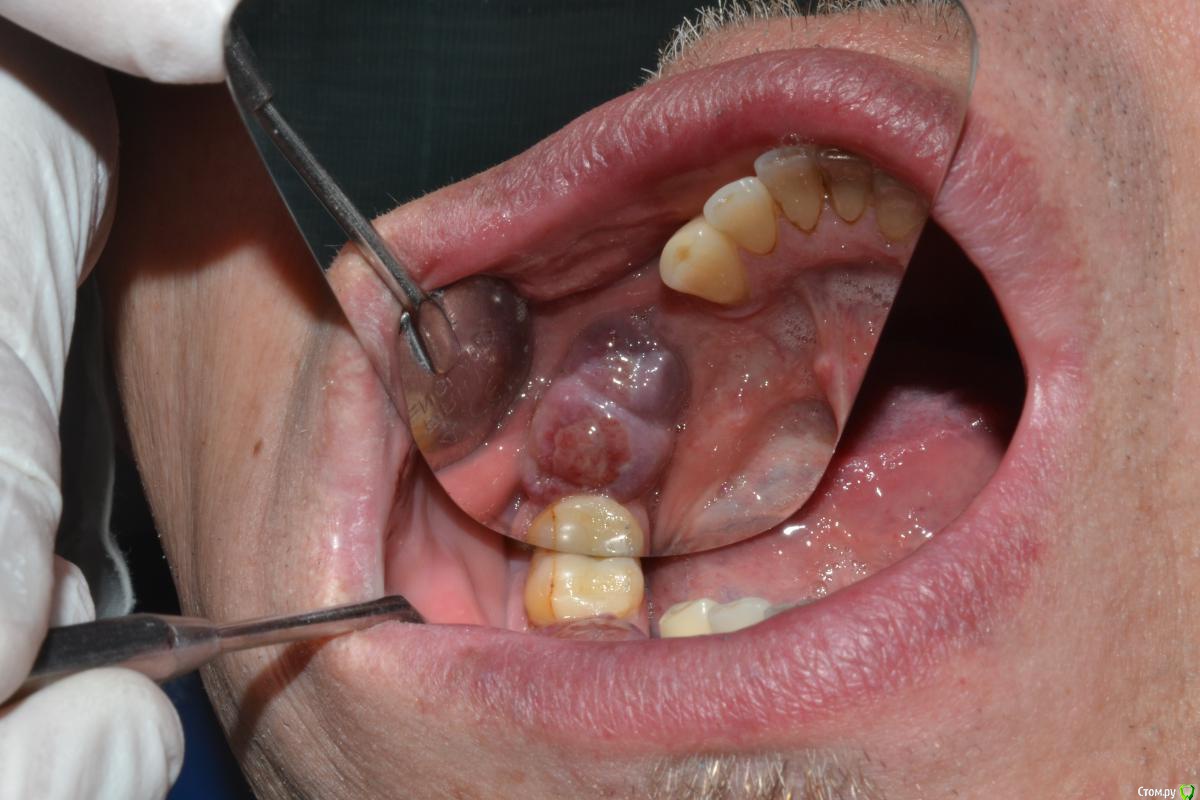

rezo47 Опубликовано 28 июля, 2015 Поделиться Опубликовано 28 июля, 2015 Добрый день коллеги! Обратился пациент на этап протезирования, имплантаты поставлены год назад в нашей клинике. Врач пациенту сказал появиться через 6 мес. но пациент не пришел, сам врач этот уже не работает. Мукозит появился около 3 мес. назад, боли нет. Отправил на ОПГ, кости нет, причем слева тоже невсе ок, но об этом позже. А пока демаю что с этим всем делать. План мой таков:- иссечь в пределах здоровых тканей;- удалить имплантаты 46;45;- контроль через 2 мес. Выслушаю любые предложения Ссылка на комментарий

Доктор Добрых Дел Опубликовано 28 июля, 2015 Поделиться Опубликовано 28 июля, 2015 (изменено) Если вести речь об удалении имплантатов, то тогда всех трёх, так как не вижу особой разницы по состоянию костной ткани между, например, 44 и 45. К тому же позиции имплантатов далеки от идеальных. На счёт иссечения согласен, на счёт удаления - может быть есть смысл сначала сделать КТ .На ОТПГ вроде язычная стенка прослеживается, может быть удастся сохранить Изменено 28 июля, 2015 пользователем Доктор Добрых Дел Ссылка на комментарий

kriokov Опубликовано 28 июля, 2015 Поделиться Опубликовано 28 июля, 2015 Справа 3 убирать надо. Как рану потом вести подумать надо. Может раскрыться линейно,выкрутить болты, убрать только грануляции с кости, потом иссечь мягкие до живых и под тампоном вести? Пац повторную имплант планирует? Представляет что за дефект будет? Язычная останется только у 44 Ссылка на комментарий

АнтонТЛТ Опубликовано 28 июля, 2015 Поделиться Опубликовано 28 июля, 2015 Слева тоже бы убрал. Справа мягкие ткани бы нее иссекал, само всё должно восстановиться после удаления имплантатов Ссылка на комментарий